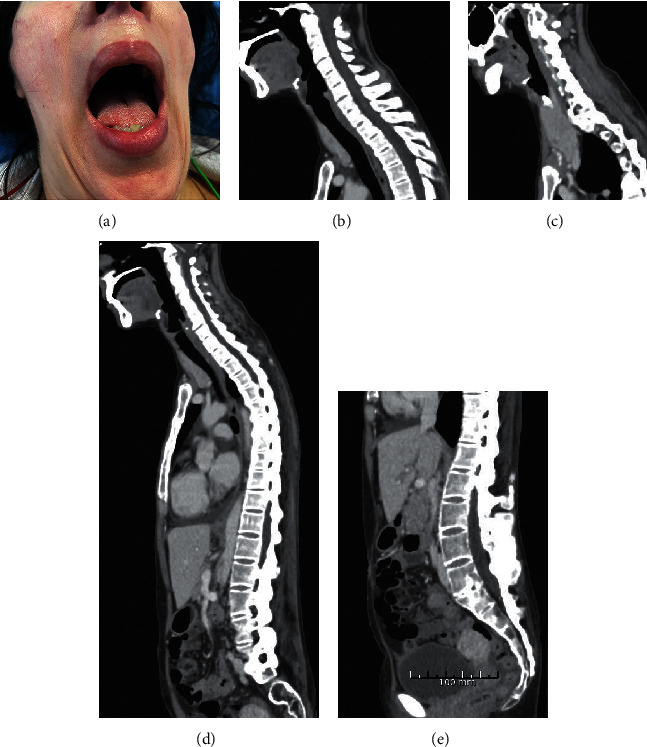

妊娠与解剖和生理变化相关,导致潜在的气道管理困难。一些孕妇有困难的气道,即使使用高角度的视频喉镜也不能插管。如果也不可能进行轴向气管插管,在灵活的支气管镜下进行清醒气管插管可能是避免更多侵入性技术的少数可用选择之一。红外线红色插管系统(IRRIS)可以帮助非专业麻醉师在这种情况下,并可能增加插管成功的机会,提高母亲和胎儿的安全性,特别是在没有耳、鼻、喉外科手术支持的医院。

Pregnancy is associated with anatomical and physiological changes leading to potential difficult airway management. Some pregnant women have known difficult airways and cannot be intubated even with a hyperangulated videolaryngoscope. If neuraxial techniques are also impossible, awake tracheal intubation with a flexible bronchoscope may be one of the few available options to avoid more invasive techniques. The Infrared Red Intubation System (IRRIS) may help nonexpert anesthesiologists in such situations and may enhance the chance of successful intubation increasing safety for the mother and the fetus, especially in hospitals without the ear, nose, and throat surgical backup.